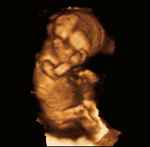

Dr. Maureen Paul, abortionist, says the abortions she performs:

“What I prefer to do is to just reach in with my forceps and collapse the skull and bring the fetus out intact.”